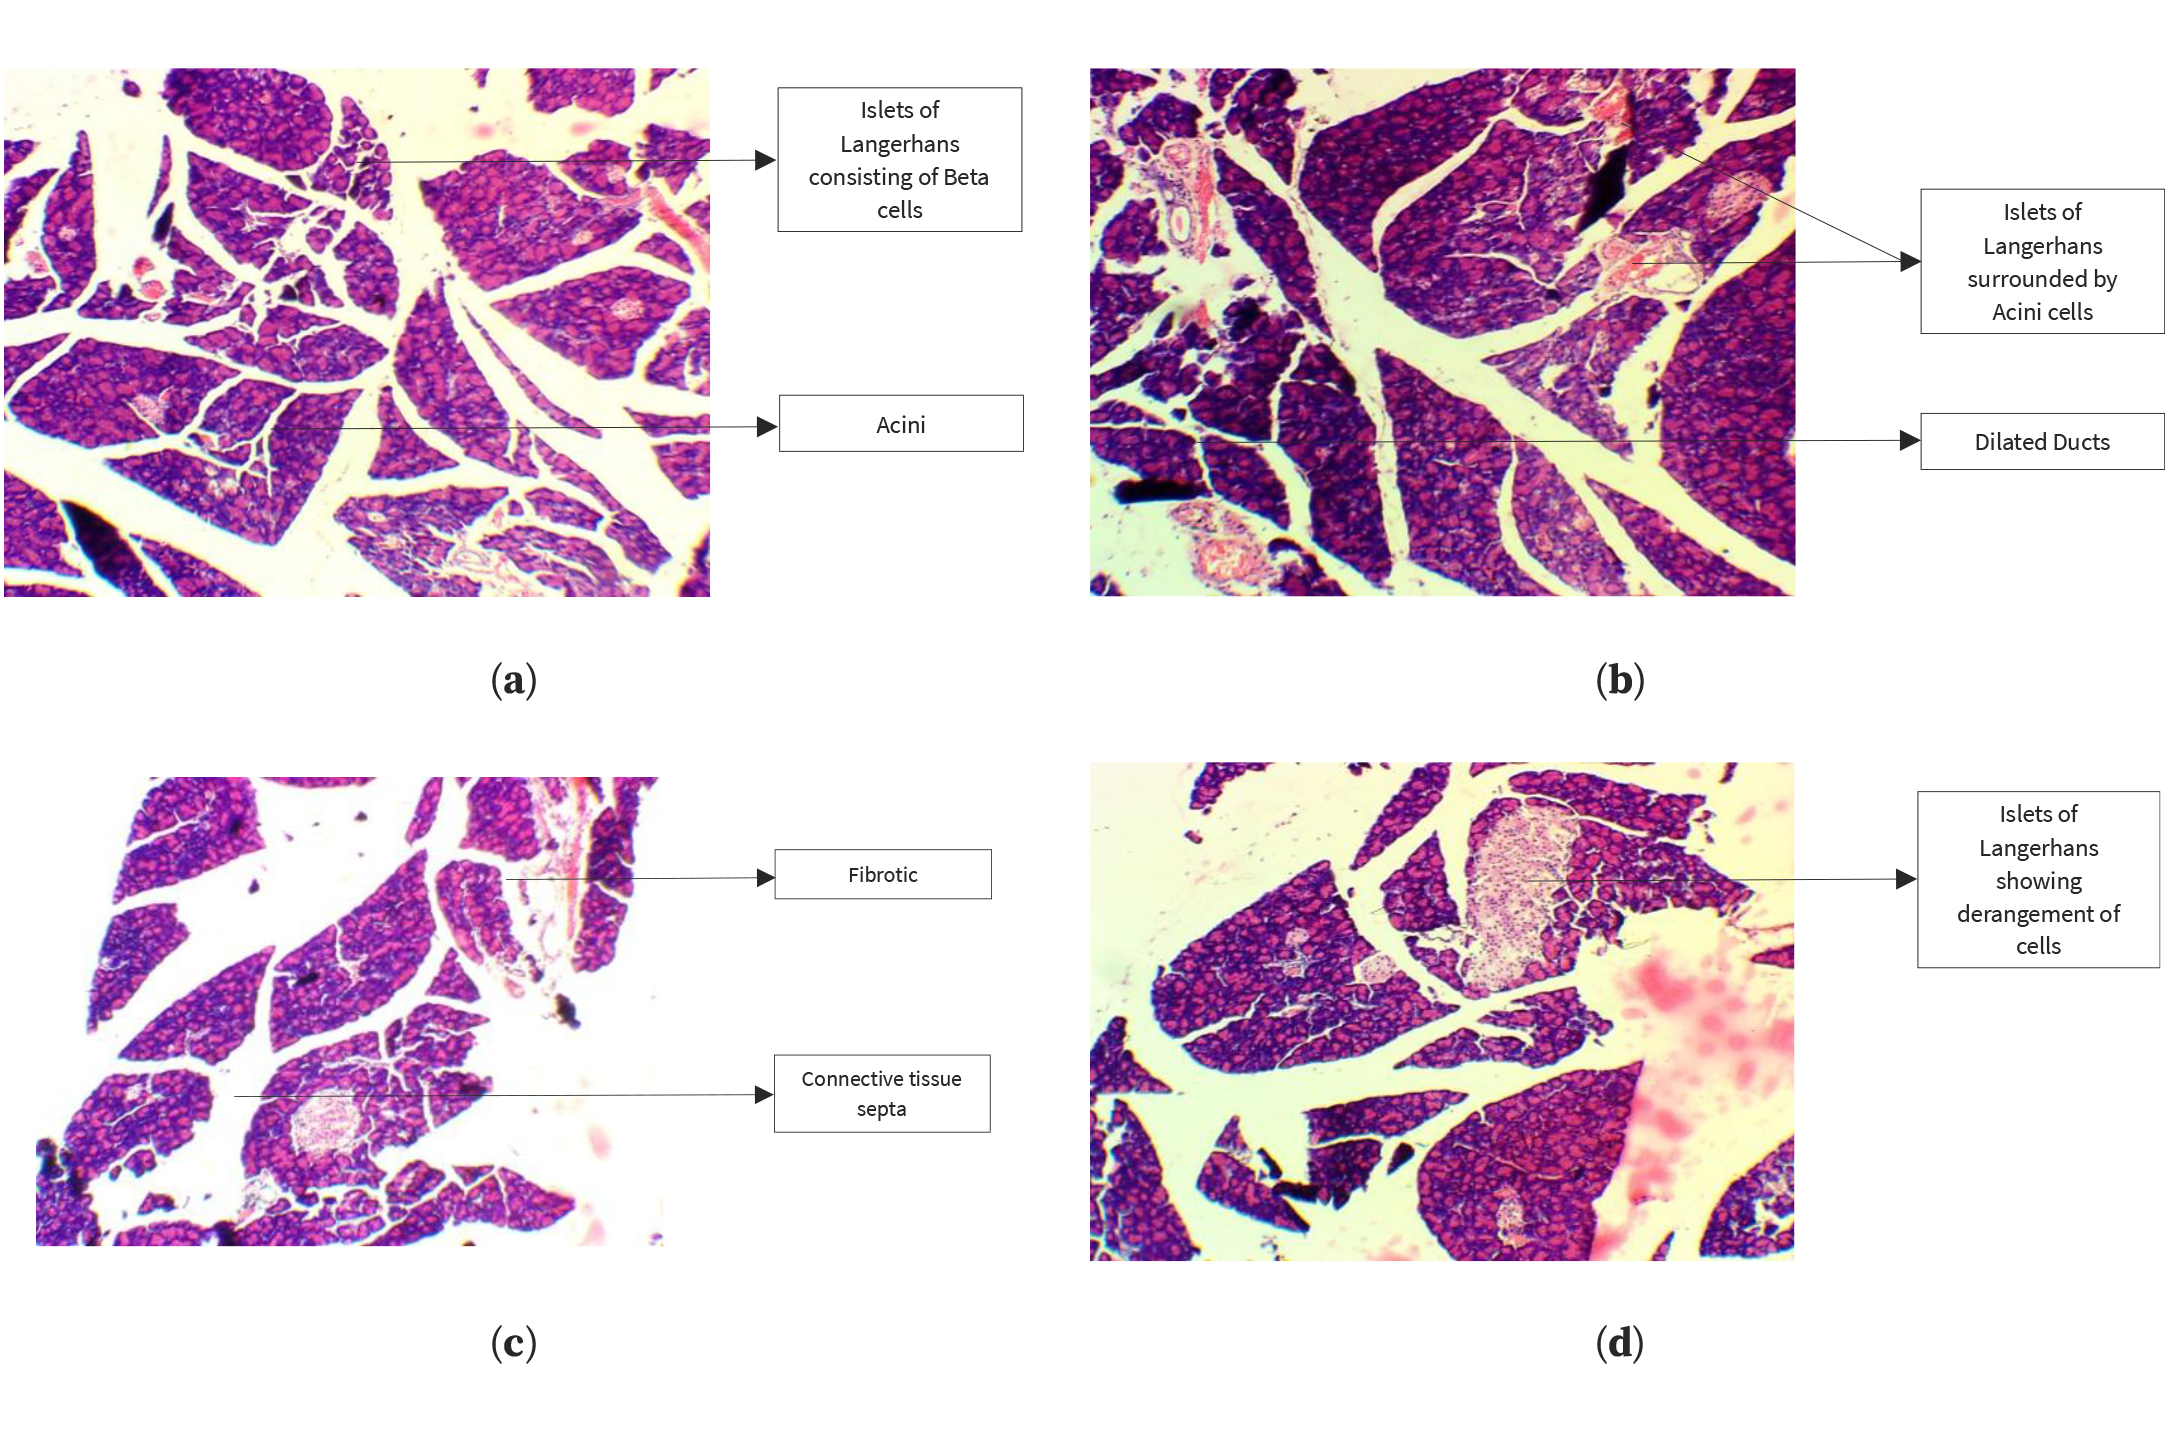

Histopathological analysis of pancreatic tissue samples revealed that the control group exhibited a normal arrangement of beta cells within the islets of Langerhans (Figure 2). In contrast, the HFrD group displayed inflammation of beta cells and abnormal enlargement of the islets, along with edema and dilated blood vessels in the pancreatic tissue. However, these adverse effects were reversed in the groups treated with kaempferol, quercetin, or QSE, with the pancreatic islet architecture preserved and reduced signs of inflammation and degeneration, thereby mitigating the metabolic disorders and pancreatic damage caused by HFrD.

Figure 2. Histopathological analysis of the pancreas in the control group (a), HFrD group (b), kaempferol-treated group (c), and quercetin-treated group (d).

Taken together, all the treated groups showed a protective trend in comparison with the HFrD-untreated group. Body weight increased progressively in all groups during the experimental period, but its magnitude of increase was significantly lower in the groups receiving kaempferol, quercetin, or QSE, with the lowest net increase being observed in the HFrD + QSE group. Systemic metabolic stress due to HFrD feeding resulted in decreased Hb levels in rats in the HFrD group, while partial recovery of its concentration was observed in the treatment groups, suggesting partial correction of metabolic imbalance. Serum ALT activity, an important biomarker of hepatocellular injury, was highly elevated in HFrD rats, while the administration of kaempferol, quercetin, or QSE resulted in a remarkable reduction in ALT levels in these groups of rats and, in some instances, a decrease in ALT levels compared with the respective control values. Histopathological examinations further confirmed the above biochemical observations. HFrD exposure resulted in vacuolar degeneration, hepatocellular necrosis and inflammatory infiltration in liver tissues, whereas the treated groups exhibited only mild degenerative changes in the hepatic tissues with preserved architecture of the liver. Similarly, tissues of the pancreas obtained from diabetic rats fed a showed inflammation of the islets of Langerhans, disruption of β-cells, and edema, whereas those in the treatment groups maintained a normal islet morphology with fewer inflammatory changes. Overall, these observations suggested that quercetin, kaempferol, and QSE had significant pancreatic protective effects by decreasing fructose-induced structural and metabolic changes in diabetic rats.